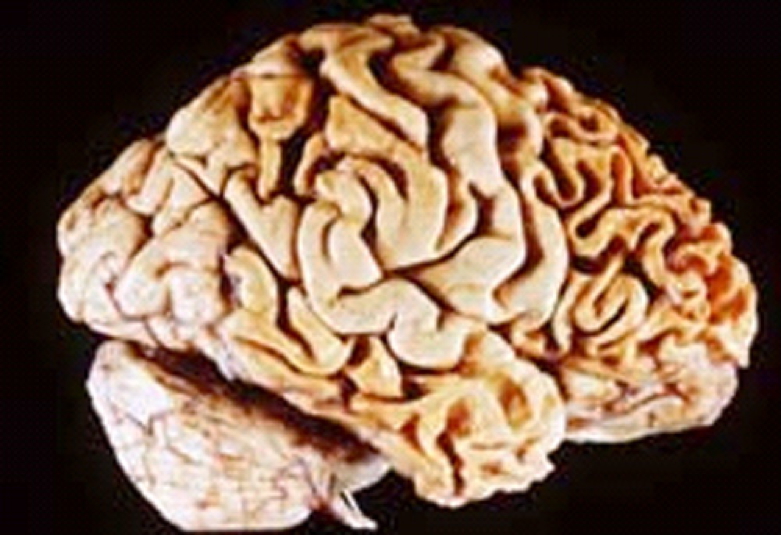

Morphology

- Severe cortical atrophy, widened sulci, narrow gyri

- Compensatory ventricular dilation (hydrocephalus ex-vacuo)